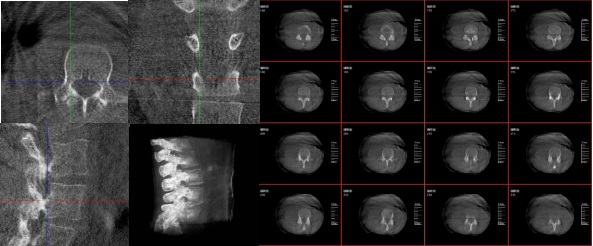

三維重建技術在醫(yī)學影像診斷領域十分重要,它是一種利用計算機軟件將二維醫(yī)學影像(如X光、CT、MRI等)轉化為三維立體圖像的技術,可以為醫(yī)生提供更直觀、更清晰的圖像信息,方便醫(yī)生從多個角度觀察病灶,從而更全面地了解病情,有助于提高診斷的準確性和效率。

三維重建技術在醫(yī)學影像診斷中的應用非常廣泛,主要包括以下幾個方面:

1.診斷疾病:通過三維重建技術,醫(yī)生可以更直觀、清晰地觀察到患者體內(nèi)的異常情況,如腫瘤、骨折等,從而更準確地診斷疾病。

2.手術規(guī)劃:在手術前,醫(yī)生可以通過三維重建技術對患者的病變部位進行詳細的觀察和分析,制定出最佳的手術方案。

3.手術導航:在手術過程中,醫(yī)生可以通過三維重建技術實時觀察手術器械的位置,提高手術的精確性和安全性。例如在關節(jié)外科手術中,存在植入物的錯位在術中不易發(fā)現(xiàn)的情況,如果在術后CT中檢查出,就不可避免地需要翻修手術,這就會增加并發(fā)癥的概率以及感染風險。而通過術中三維影像設備PLX C7600的檢查,可以立即發(fā)現(xiàn)植入物的錯位,減少不必要的第二次手術。